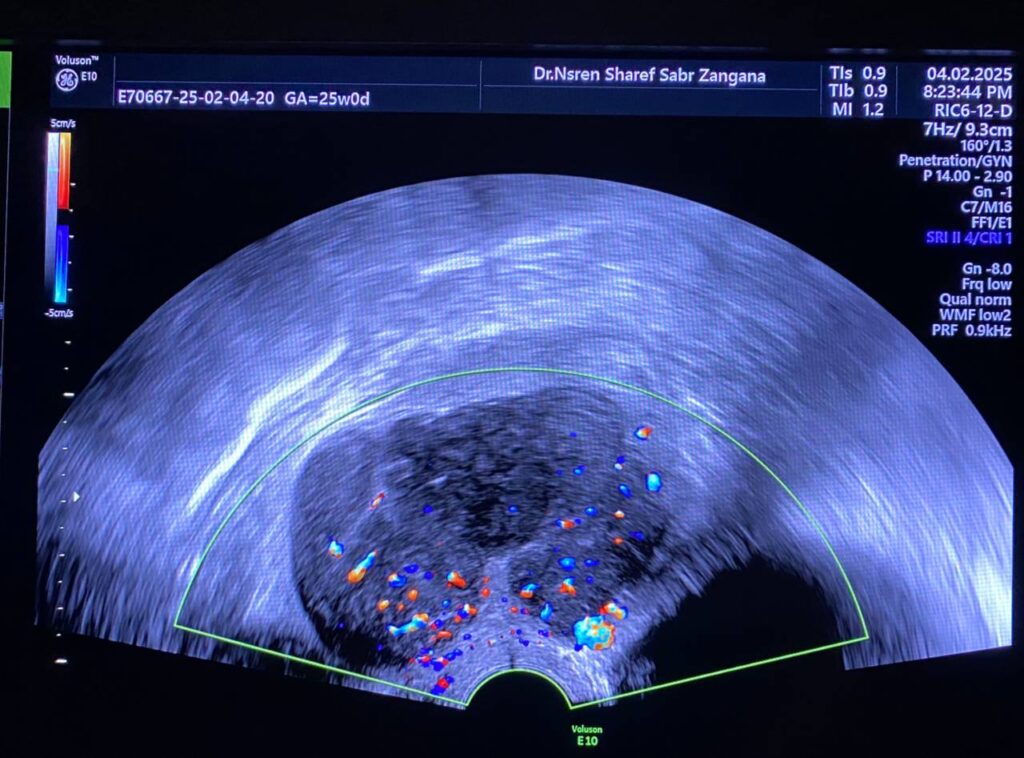

Bulky uterus, endometrial lining thickness 2mm, occupied by clear avascular fluid , mostly due to mass effect , Presence of hypoechoic solid mass 68x48mm ,vascular on color Doppler , Color Score 4 (Hyper vascular) , within right sided posterior submucosal subserosal region , associated with other two smaller masses seen on the anterior wall , their sizes are 19x18mm& 8x12mm (Metastasis? Lymphoma ??) or other suspicious masses

Associated with Presence of pathological lymph node in the right para iliac region size 35x24mm& other pathological lymph node in the left para iliac region 35x21mm , lymphoma or secondary metastasis can not be excluded